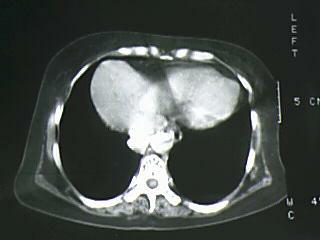

以下是引用bmw011在2009-4-14 19:14:00的发言:[br]右肺继发型肺结核---纵隔淋巴结多发钙化----左肺支扩。支持

以下是引用杀毒软件在2009-4-14 17:52:00的发言:[br]考虑---右肺继发型肺结核---纵隔淋巴结多发钙化----左肺支扩

以下是引用黑白光影在2009-4-14 20:36:00的发言:[br]右肺继发型肺结核;左下慢性支气管炎性病变。